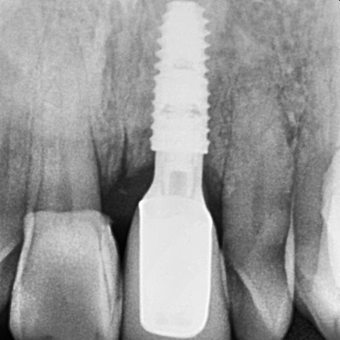

임플란트 식립

50대 남성 환자분으로, 뿌리가 거의 드러난 왼쪽 위 앞니는 잇몸뼈도 많이 녹고, 잇몸도 망가진 상태였습니다.

임플란트만 심을 경우 티타늄 뿌리가 보이거나 치아 보철이 지금처럼 길게 보여 비심미적일 것으로 예상되었습니다.

지방에서 오신 만큼, 내원 횟수도 최소화하고 심미적인 만족감도 높이기 위해

치아 발치와 함께 잇몸뼈 이식, 임플란트 식립, 잇몸이식을 한번에 신속하게 진행하였습니다.